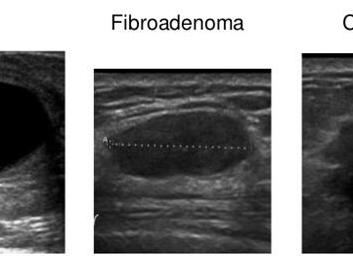

На фото представлена УЗИ-картина фиброаденомы (слева) и рака (справа) молочной железы. Фиброаденома выглядит как четко-ограниченное гипоэхогенное образование с ровными или дольчатыми контурами в отличие от рака. Злокачественная опухоль характеризуется неровными краями и атипическим ростом. Если образование оценивается как подозрительное, обязательно должна быть выполнена последующая тонкоигольная биопсия узла.